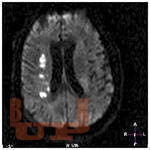

Книга посвящена теме доминантности / субдоминантности полушарий

головного мозга в отношении высших психических функций. Описаны симптомы игнорирования противоположной стороны, нарушения схемы тела,

ориентации в окружающем пространстве, лицевая агнозия, анозогнозия у

больных с правополушарными очаговыми поражениями мозга. Проведены

исследования эмоциональной сферы данной категории пациентов. Наряду с

этим в книге показана эффективность проведенных реабилитационных мероприятий.